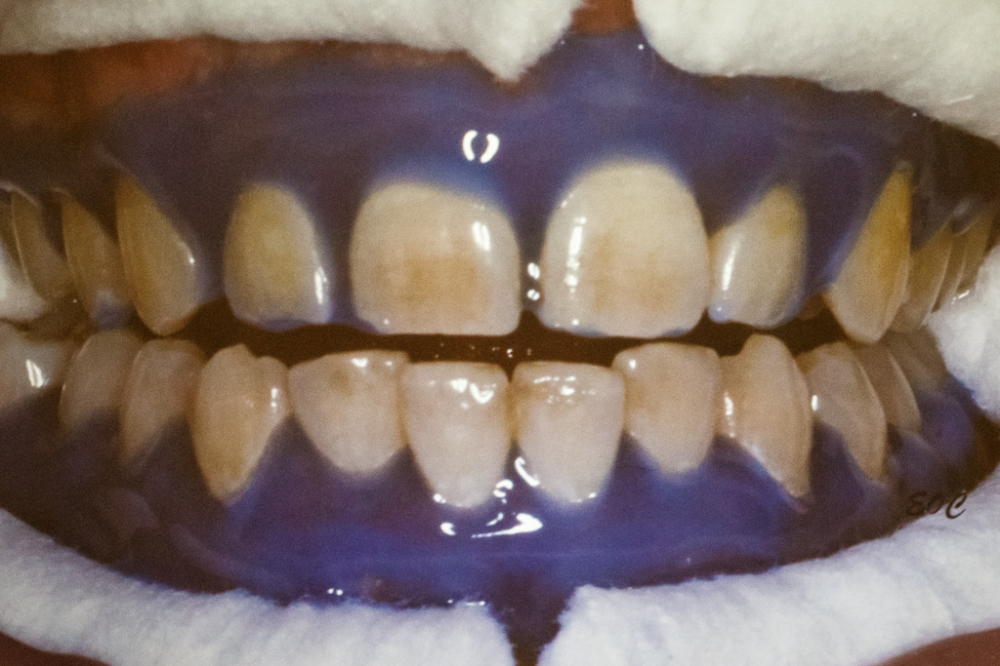

Основная задача данного курса - помочь поставить руку врачу и рассказать докторам о самых важных аспектах отбеливания зубов. Ольга Сергеевна с поставленной задачей справилась блестяще. Практическая часть мастер-класс по отбеливанию проводилась системой Bleach'n Smaile.